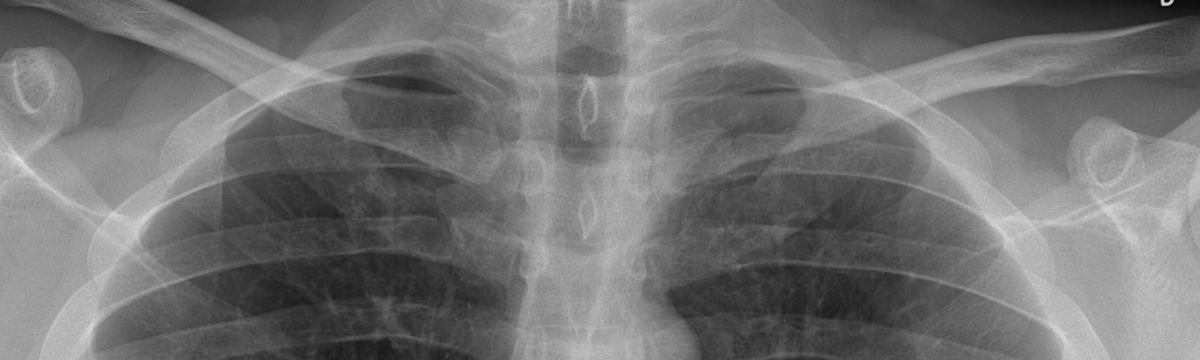

Image Critique Series – Part 1: Beginner Elbow - Elio Arruzza, UniSA; Lower Limb – Patrick Tito, Canberra Health Services; Chest – Adam Steward, Western Health.